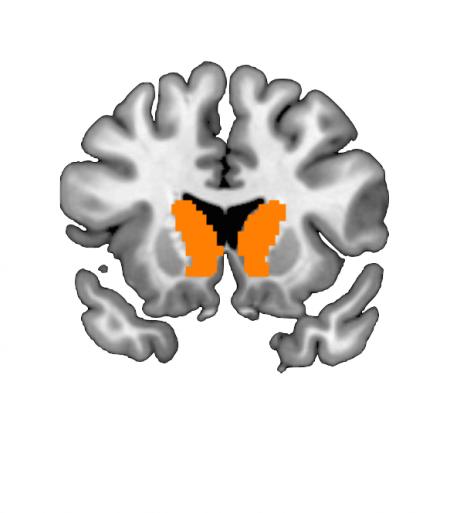

By combining computational modeling of the data from the "Self" behavioral trials with the fMRI data, the researchers determined that a region of the brain called the caudate nucleus responds to the degree of risk in the gamble; for example, a riskier gamble resulted in a higher level of observed activity in the caudate nucleus, while a less risky gamble resulted in a lower level of activity. Additionally, the more likely the participants were to make a gamble, the more sensitively activity in the caudate nucleus responded to risk. "This showed that, in addition to the behavioral shift, the neural processing of risk in the caudate is also altered. Also, both the behavioral and neural responses to taking risks can be changed through passively observing the behavior of others," Suzuki says.

The "Predict" behavioral trials were designed to test whether a participant could also learn and predict the risk-taking preferences of an observed peer. Indeed, the researchers found that the participants could successfully predict these preferences--with the learning process occurring even faster if the participant's risk-taking preferences mirrored those of the peer. Furthermore, the fMRI data collected during the "Observe" trial showed that a part of the brain called the dorsolateral prefrontal cortex (dlPFC) was active when participants were learning about others' attitudes toward risk.

The researchers also found differences among participants in functional connectivity between the caudate nucleus and the dlPFC that were related to the strength of the contagion effect--meaning that these two brain regions somehow work together to make a person more or less susceptible to the contagiousness of risk-taking behavior. The work provides an explanation of how our own risk-taking behaviors can be influenced simply by observing the behaviors of others. This study, Suzuki says, is the first to demonstrate that a neural response to risk is altered in response to changes in risk-taking behavior.